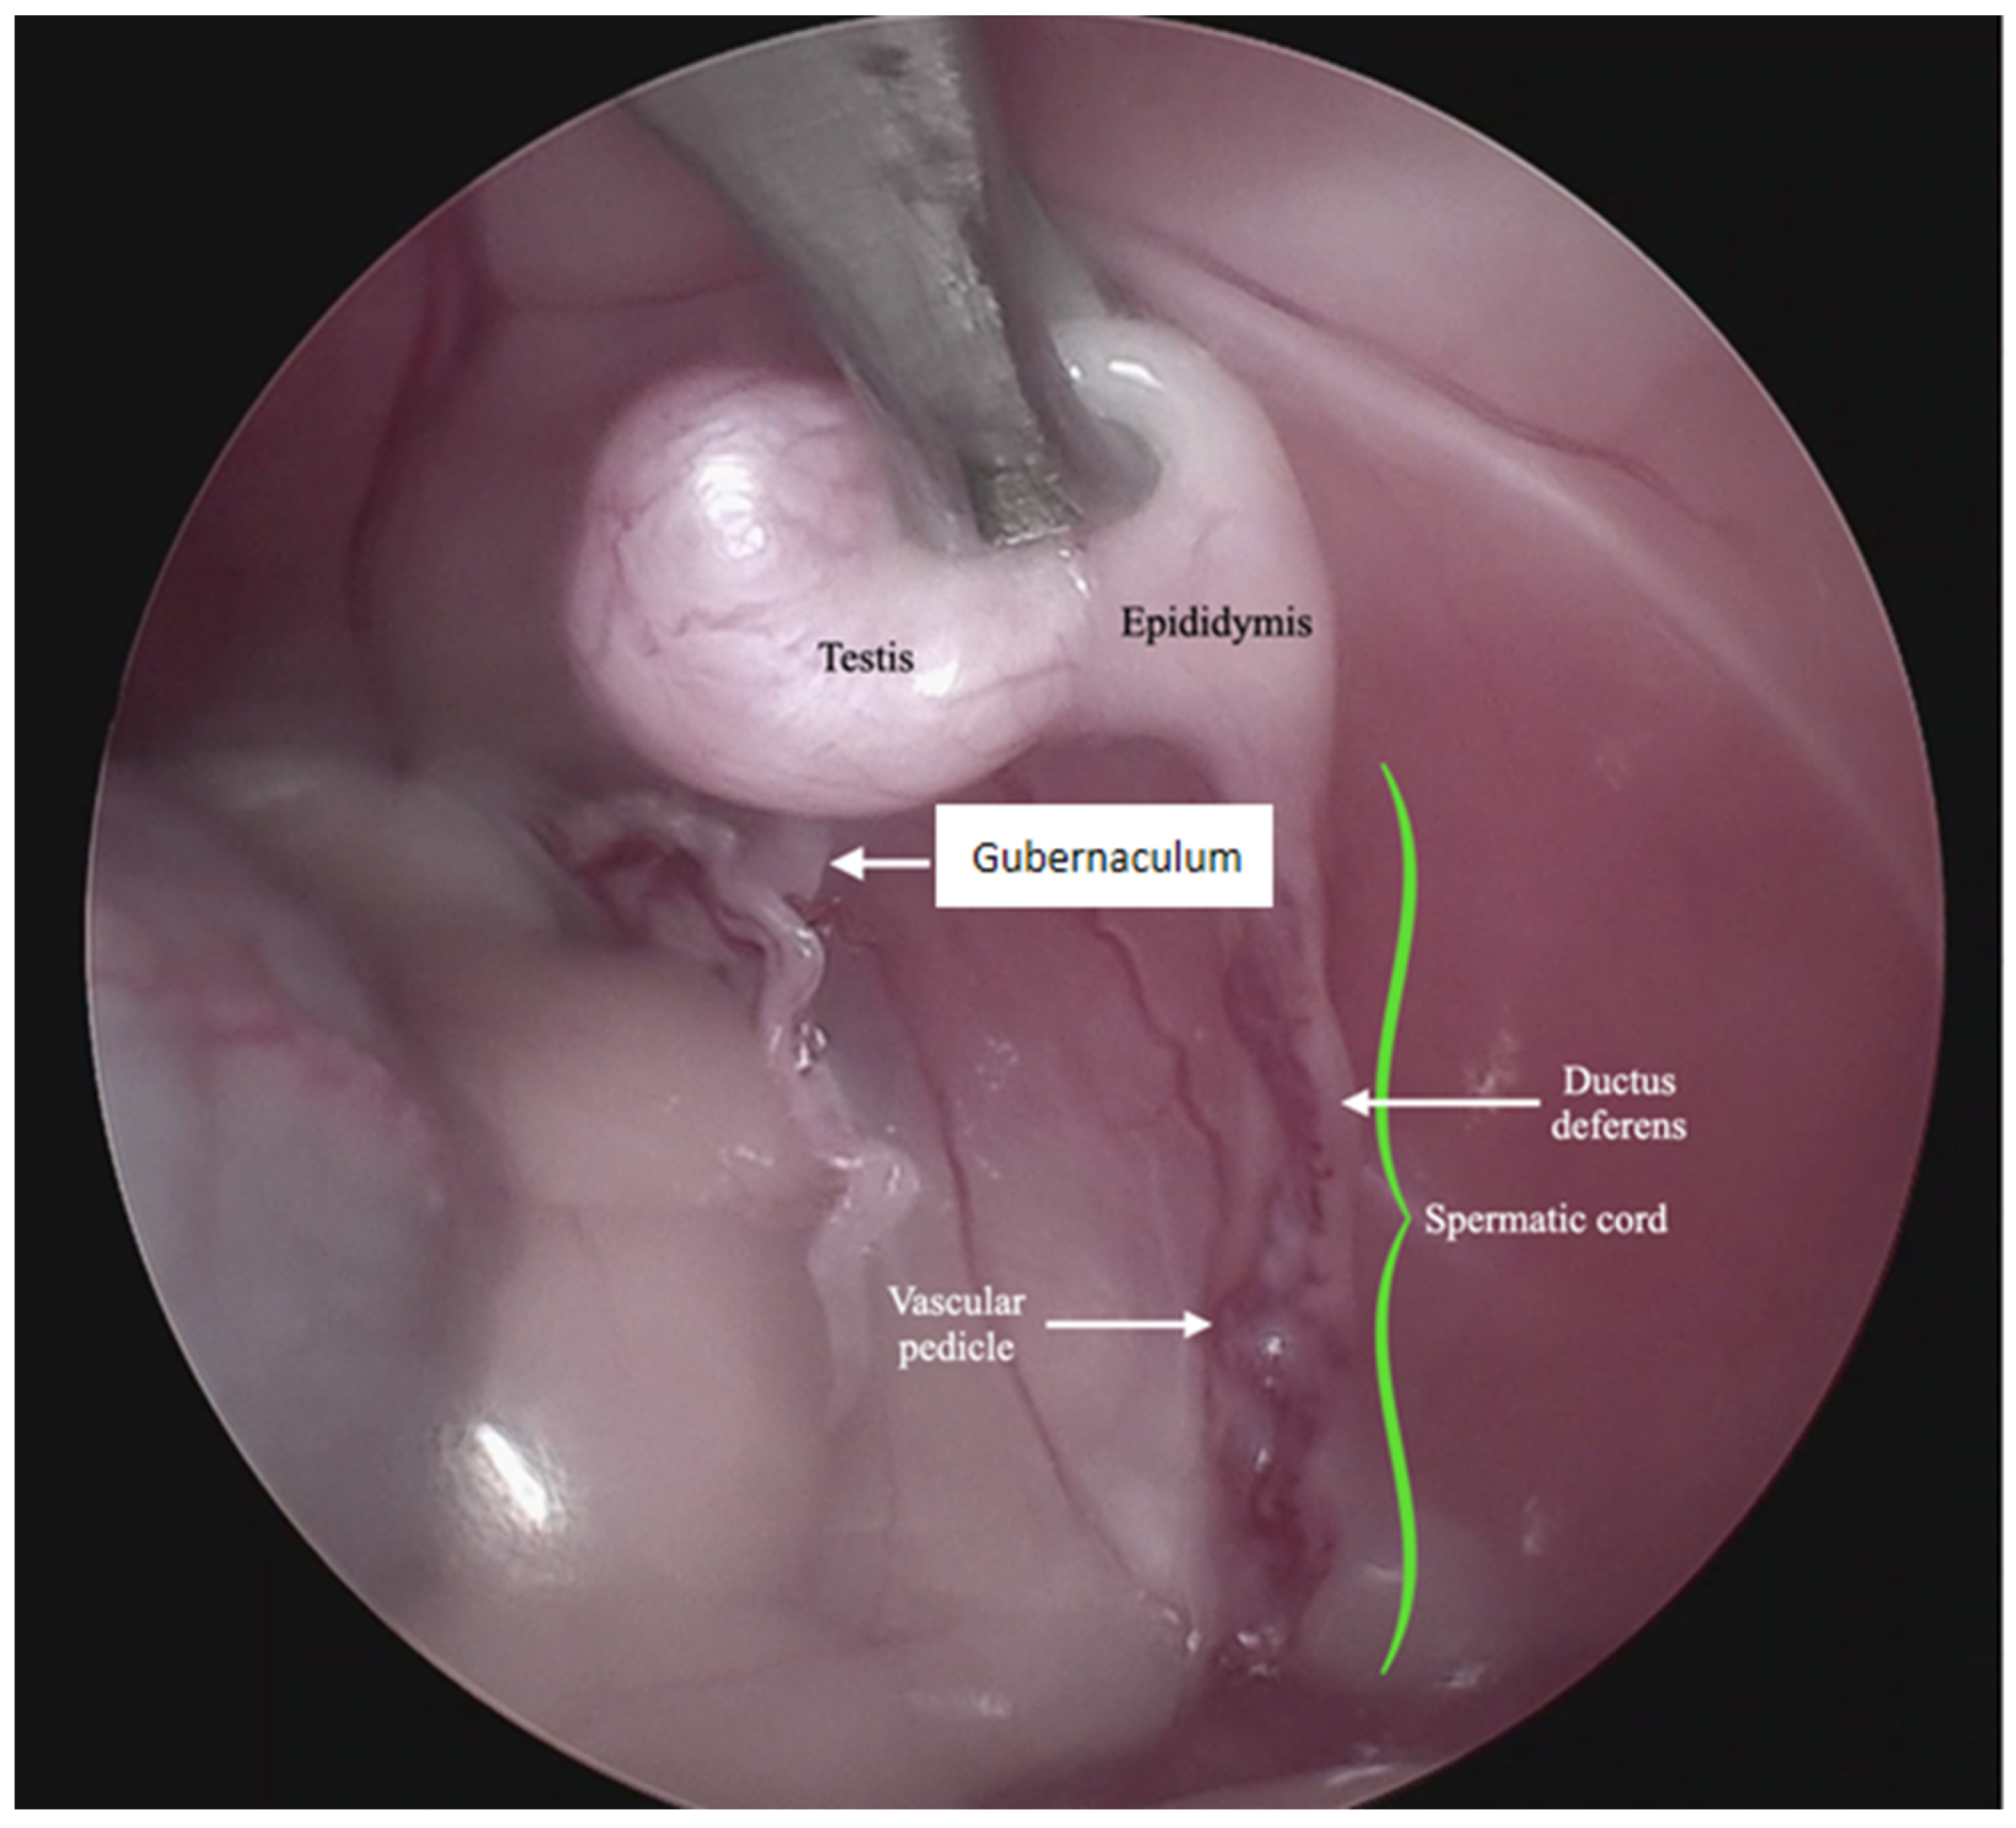

For the surgical procedure, in all cases, inhaled anesthesia was used, and anesthesia monitoring was performed by qualified personnel. In all cases, the main trocar was placed just caudal to the umbilicus using a Hasson technique in 10 cats, modified-Hansson in six cats, and the Veress needle technique in three cats. A small skin incision (<10 mm) was made at this site, and subcutaneous tissues were dissected to visualize the external rectus abdominis sheath; a small stab incision was made into the peritoneal cavity. In 16 cats, a 5 mm trocar was inserted through the incision, and a 6 mm trocar into the remaining 3 cats. The capnoperitoneum was achieved at a rate of 1–2 L/min to an intrabdominal pressure of 7–9 mmHg. A rigid 5 mm telescope with 0° or 30° angle vision was inserted through the trocar, and the abdomen was explored systematically. When an abdominally retained testes was detected, a second access port with a 5 or 6 mm trocar was inserted in a caudal position and slightly lateral to the retained testis, and particularly in the case of the three bilaterally cryptorchid cats, the second trocar was inserted in the center of the caudal abdomen. The second trocar placement was performed with the use of direct visualization through the laparoscope, and transillumination of the abdominal wall was used to avoid blood vessels. To be able to work with two trocars, external suture was used to suspend the testis. The size of the needle was dependent on the size of the animal but had a curvature and sufficient length to allow comfortable entry and exit through the abdominal wall. In the current clinical cases, a 3/8 circle reverse cutting needle ranging from 24 to 30 mm length was commonly used. With transillumination, the most appropriate place to insert the needle was located, avoiding vascularized areas. First, the needle was passed through the abdominal wall, under direct endoscopic visualization and then passed through the testis carefully avoiding vascular structures, and ultimately pulling the needle out through the abdominal wall again. The suture was secured externally with the help of a hemostat, thus fixing the testis to the abdominal wall. In three cases, a percutaneous grasping technique was performed using an open-loop grasper that allowed the testis to be fixed to the abdominal wall with a single puncture; and in three cases, a third port was implemented with two paramedian trocars. With these maneuvers, the detailed visualization of the vascular pedicle, the spermatic cord, and the gubernaculum was achieved (Figure 1 and Figure 2).

Figure 2.

Endoscopic image of the anatomical structures in the intra-abdominal testis.